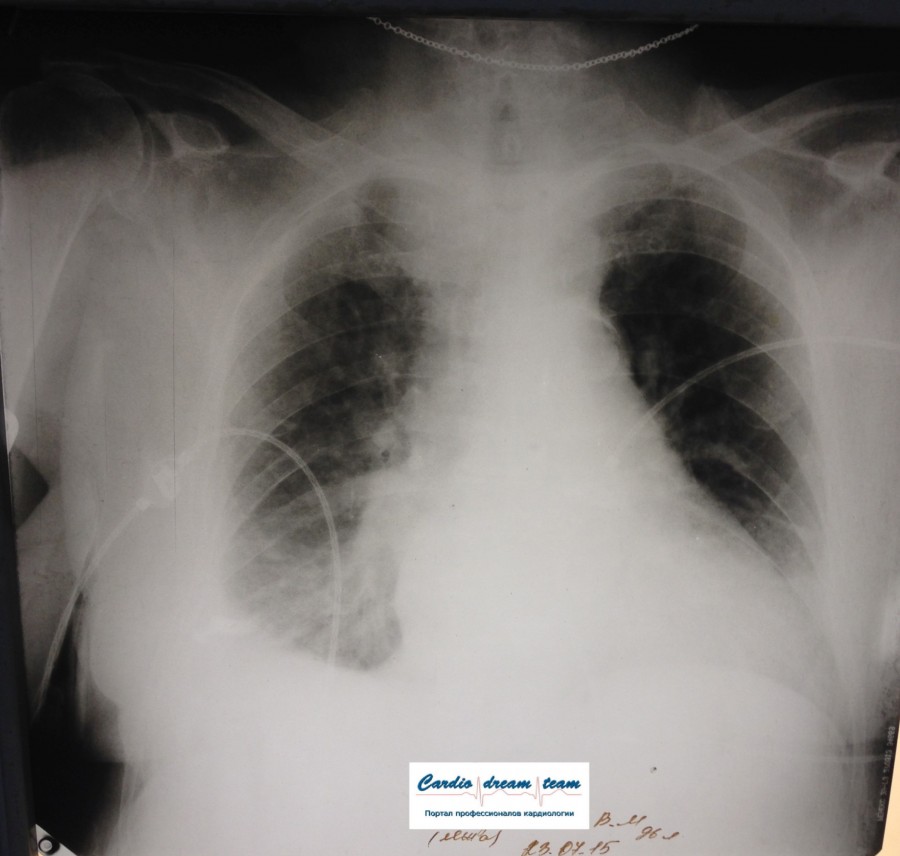

Не обсуждалась Дата 23-ИЮЛ-15 ОПИСАНИЕ: Проведена рентгенография органов грудной клетки в прямой проекции, положение лежа, условия ПИТ Легочные поля: неравномерно прозрачны за счет сосудистого обогащения, в базальных отделах с обеих сторон, отмечается сгущение легочного рисунка, за счет гиповентиляции, в плевральных полостях жидкость Легочный рисунок: Изменен по смешанному типу: обогащен за счет сосудистого компонента, деформирован за счет склероза. Корни: бесструктурны, расширены за счет сосудистого компонента, обогащены Синусы: определяется наличие жидкости по линии 5 ребра Сердце: широко лежит на диафрагме отмечается расширение границ сердечной тени влево, вправо экг-электроды. ЗАКЛЮЧЕНИЕ: Рентген-признаки 2-х стороннего гидроторакса с гиповентиляцией базальных сегментов.. Признаки застоя по МКК 2 степени (умеренно выраженный). Пневмосклероз. Р-признаки гипертрофии левого желудочка сердца. Склероз аорты.

IMG_4339--.jpg [ 717.06 KiB | Просмотров: 29307 ]